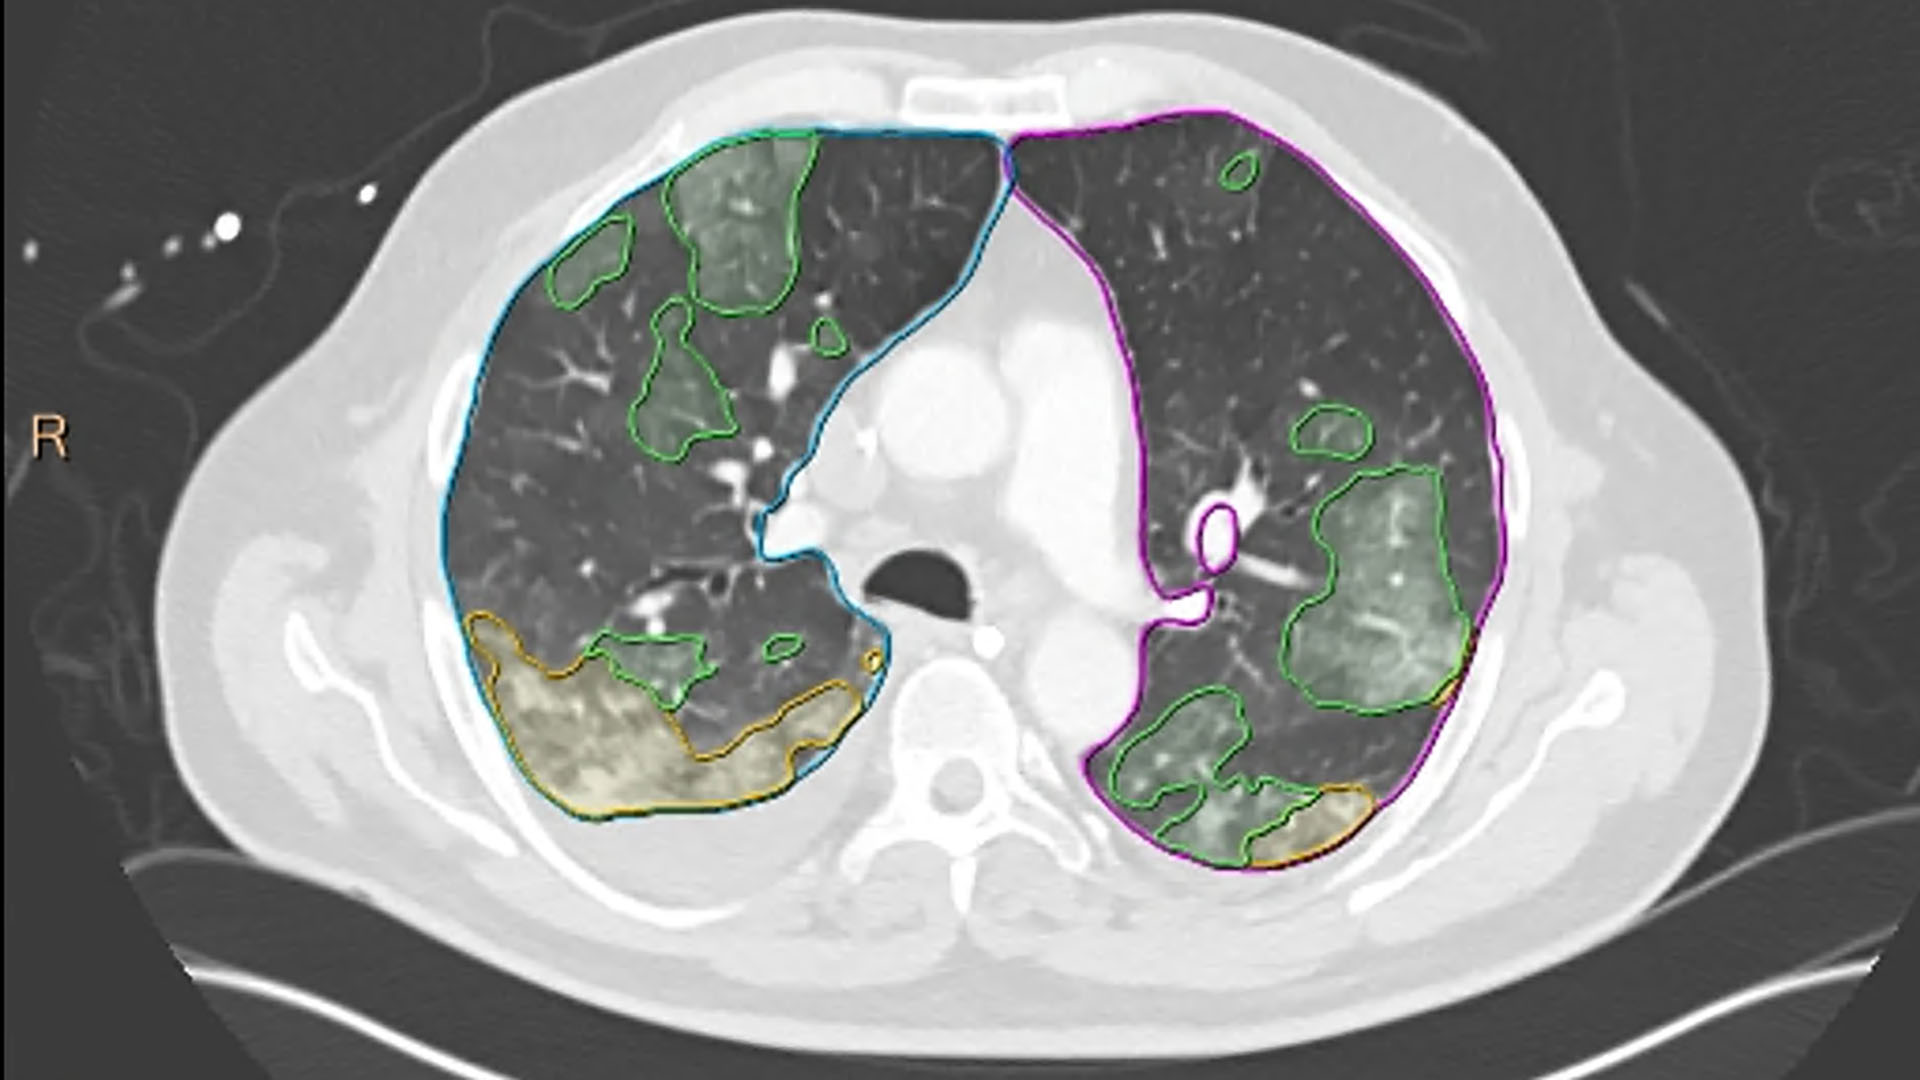

CT Pulmo Auto Results [5] – Featuring AI algorithms trained on complex pulmonary CT scans, including those of COVID-19 patients, CT Pulmo Auto Results software performs automatic lung segmentation and lesion segmentation, together with classification of ground glass opacities/consolidation. Its automatically generated reports include volume summaries and lesion distribution data to help in the quantitative assessment of pulmonary infiltrates, enhancing diagnostic confidence without increasing reading time.

CT ClearRead™ CAD Lung Nodule Analysis [6] – featuring AI-based detection and characterization for various nodule types including solid, part-solid and ground-glass lung nodules, enabling to perform nodule searches 26% faster and detect 29% of previously missed nodules [7].